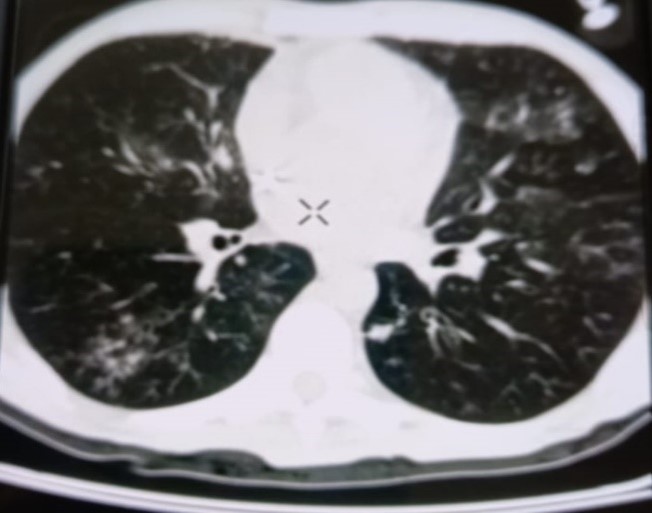

При проведении рентгенологического исследования органов дыхания в динамике спустя 2 недели с момента начала терапии данные компьютерной томографии высокого разрешения указали на следующие изменения: на фоне очаговой диссеминации в легких значительно увеличились по площади участки "матового стекла" в верхних долях обоих легких (описанные зоны неоднородные, сливные); площадь поражения легочной ткани - около 35-40%. В средних и нижних отделах легких с двух сторон выявлялись многочисленные перибронхиальные очаги до 3 мм в диаметре по типу «дерево в почках». В S 6 справа определялась зона альвеолярной инфильтрации. Выпот в плевральных полостях не определялся; внутригрудные лимфоузлы не увеличены. Заключение: признаки двусторонних полисегментарных интерстициально-инфильтративных, диссеминированных мелкоочаговых изменений легких, средняя вероятность вирусной пневмонии (в том числе COVID-19), в сочетании с диссеминированным процессом в легких (рис. 1-4).

Рисунок 1

Рисунок 2

Рисунок 3

Рисунок 4

Рис. 1-4. Компьютерная томограмма пациента Т., с ВИЧ: чередование участков «матового стекла» с диссеминированным процессом, инфильтрацией легочной ткани справа, наличие симптома «дерево в почках» (респираторный бронхиолит).